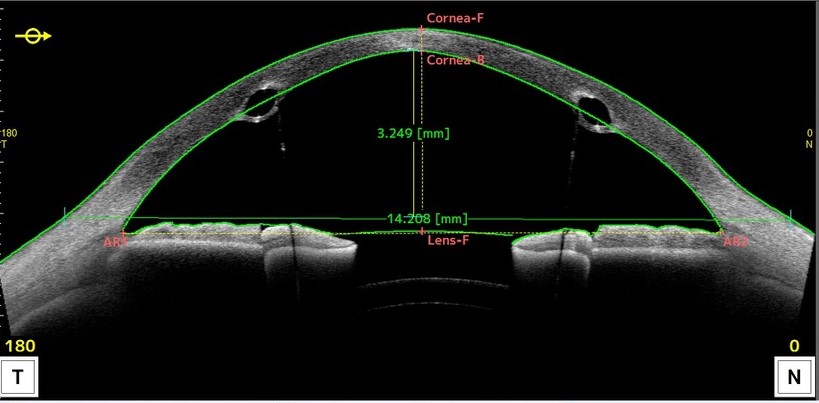

検査

細隙灯顕微鏡検査や角膜形状検査を行います。細隙灯顕微鏡検査ではある程度突出が強くなってからでなければ判断がつかないため、初期の段階では角膜形状検査が重要になってきます。この検査で、角膜中央部や中央よりやや下方の角膜のカーブが急な場合は、円錐角膜と診断されます。